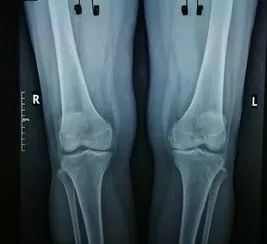

1、外傷骨頭——粗看X光片、細看CT、核磁看不清

3、關節——X光片、核磁都適用

一般如果想要看看關節的大體形態、關節間隙有沒有變窄、有沒有骨刺,拍個X光片最好。但是如果懷疑是否有韌帶、半月板損傷,還是要拍個核磁。因為韌帶、半月板都是屬于軟性組織,核磁看的更清楚。